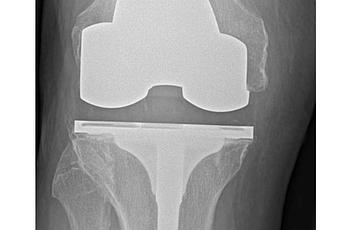

2 des chirurgies les plus courantes : les remplacements de la hanche et du genou sont aujourd’hui 2 des chirurgies les plus courantes et les plus efficaces. Pourtant, ces interventions restent parfois, comme toutes les interventions, sujettes à complications. Les principales causes d’échec sont ainsi l’infection, la fracture, l’usure normale ou la réaction aux particules usées de la prothèse. Dans nombre de ces cas, les patients nécessitent une chirurgie de révision encore plus sujette à l’échec que leur chirurgie primaire. Il est donc essentiel pour les patients et leurs chirurgiens orthopédiques de prendre en compte, dès le bilan de départ, la durée « de vie » de l’arthroplastie de la hanche ou du genou. De plus l’intervention, en fonction de ce critère, devient alors de plus en plus pertinente pour un plus grand nombre de patients en regard de l’augmentation de l'espérance de vie en bonne santé.

Des variations considérables en fonction des types d’arthroplasties : un remplacement de la hanche comprend principalement 2 composants (col, cavité) mais reste variable dans la manière dont ces pièces sont fixées à l'os, ainsi que dans les matériaux utilisés pour consolider la surface d'appui. Idem pour l’arthroplastie du genou, l’arthroplastie totale va remplacer toute la surface articulaire du patient, tandis qu'une prothèse de genou unicondylienne ne remplace que la partie endommagée du genou. Bref, les variations sont considérables en matière d’arthroplasties de la hanche et du genou, cependant ces facteurs ont bien été pris en compte dans l’analyse.